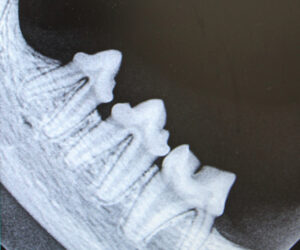

Von Impfungen bis zur Knochenchirurgie, wir helfen Ihren Tieren bei kleinen und großen Erkrankungen.